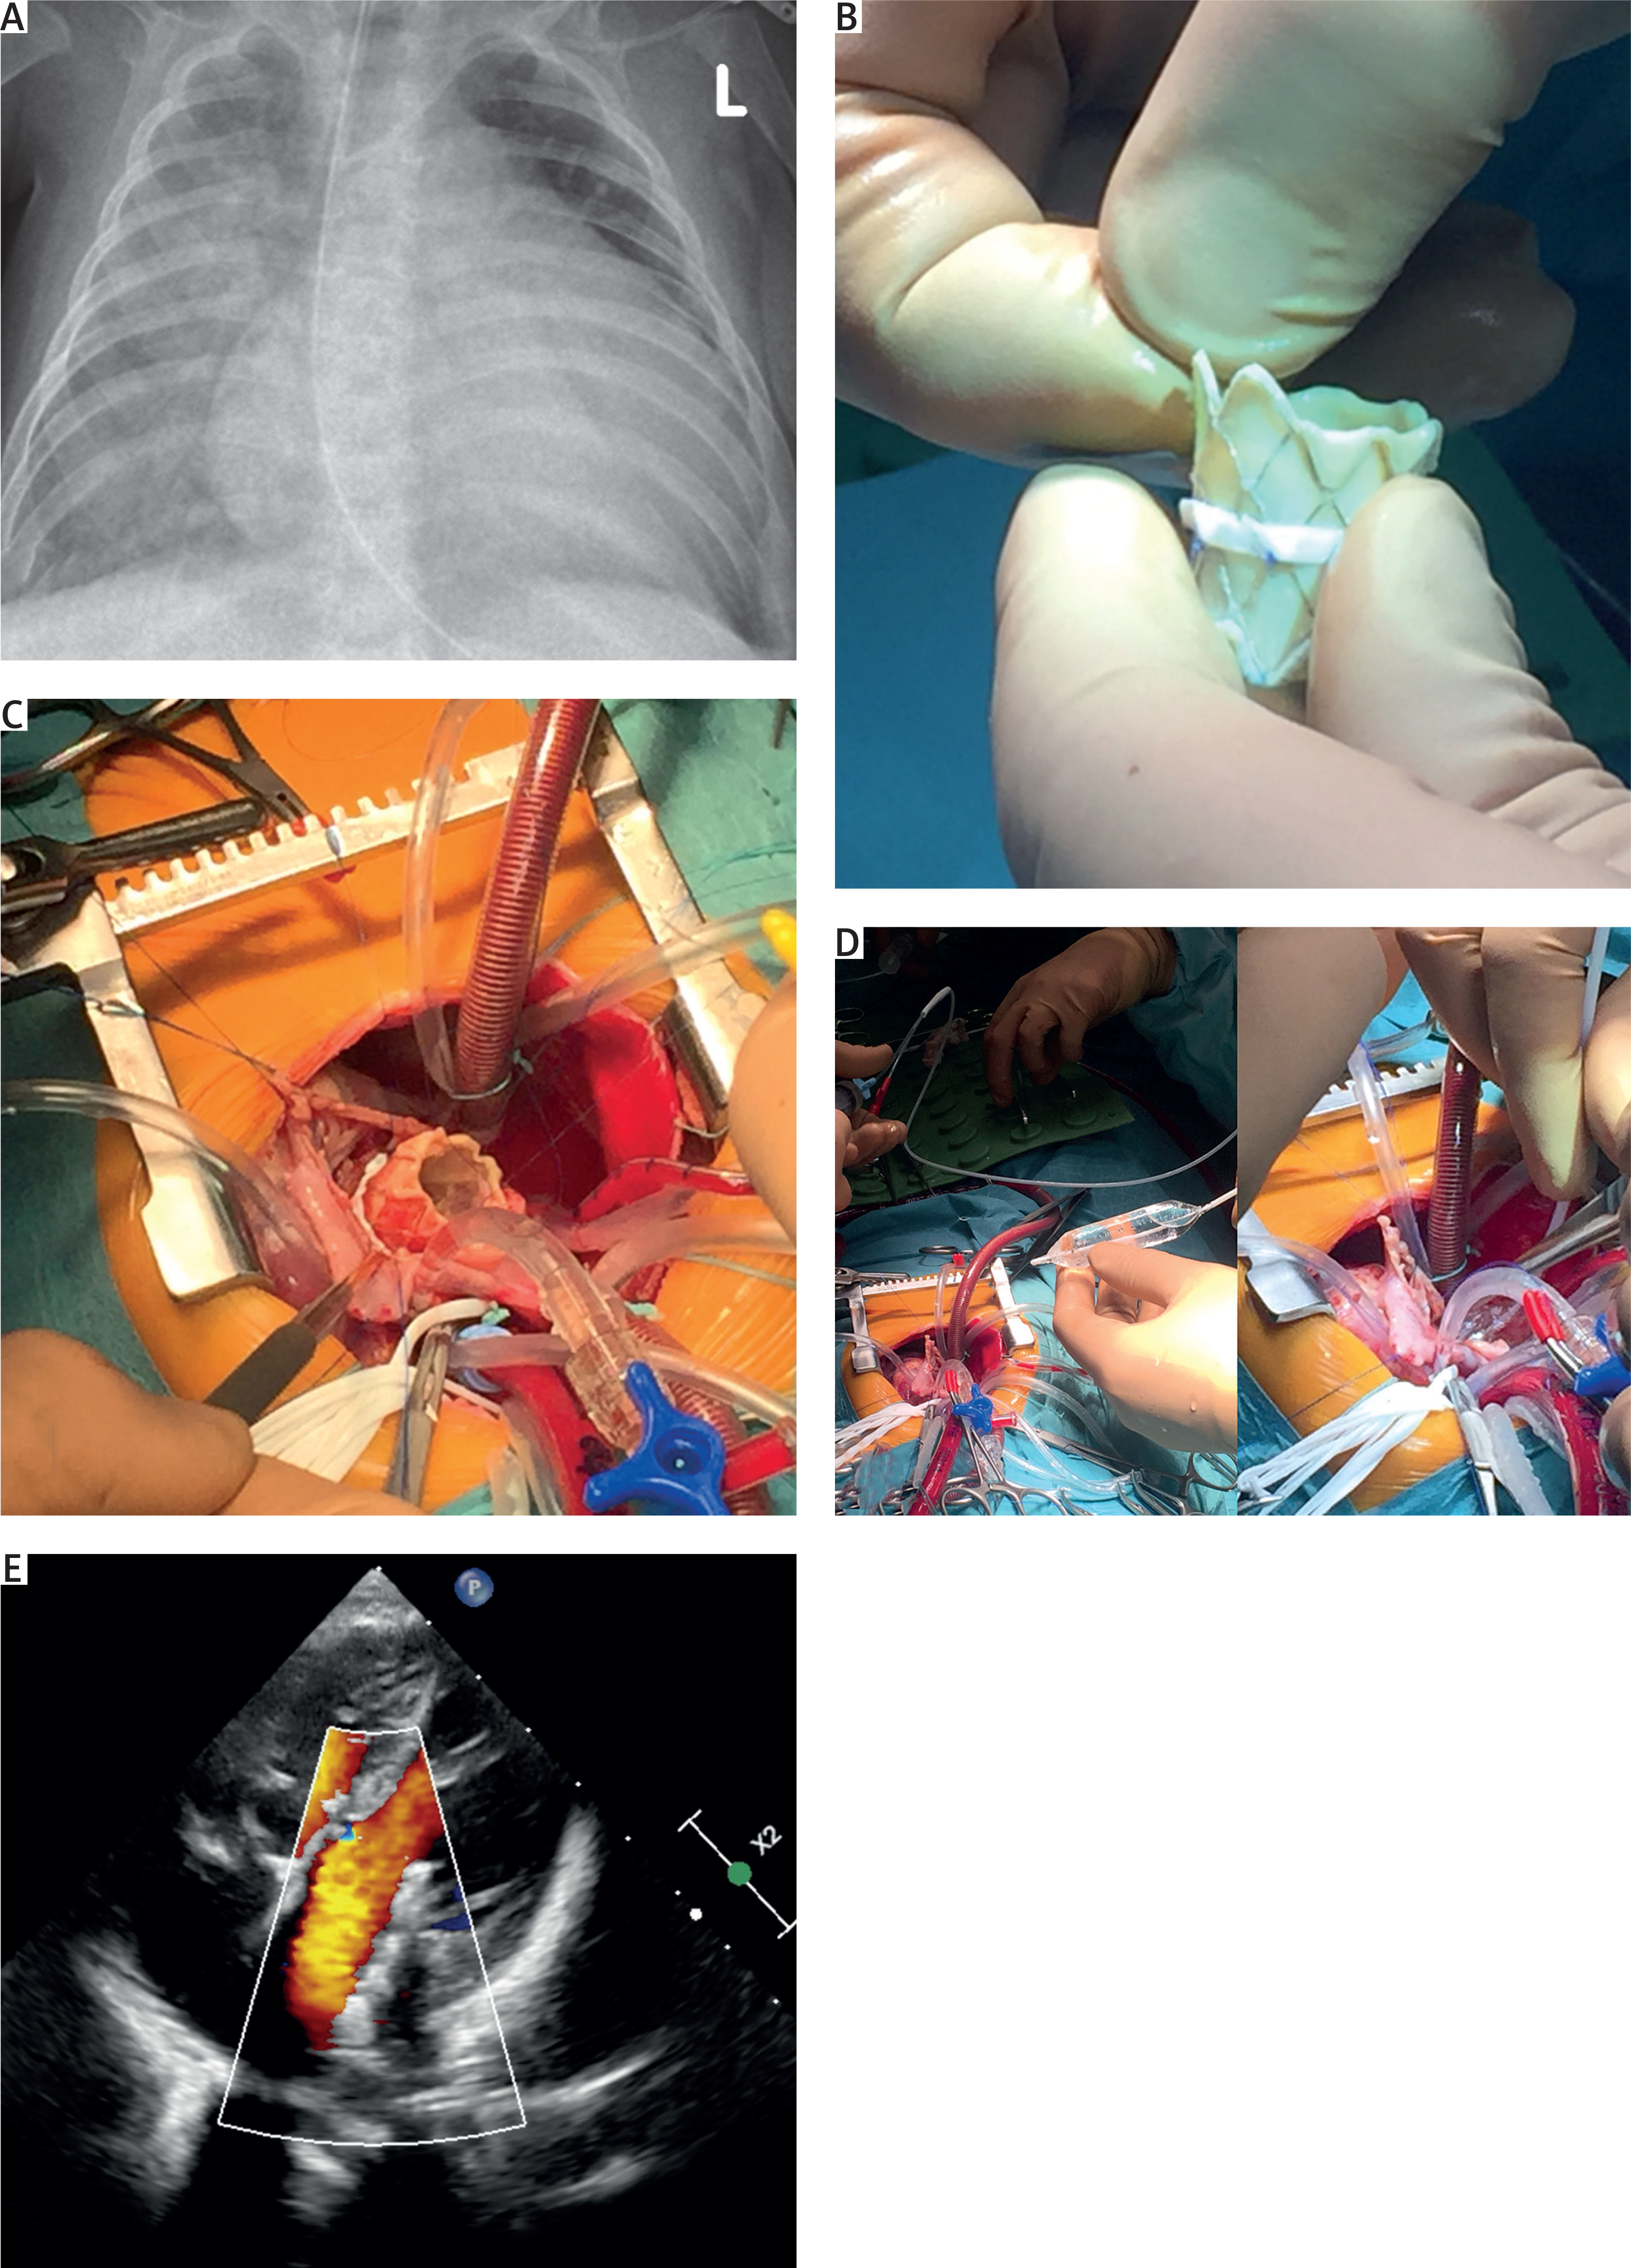

The child was admitted to the pediatric cardiac surgery unit in critical general condition, nasally intubated, with borderline decompensation, hepatomegaly and peripheral edema (Figure 1 A). Preoperative echocardiography confirmed CAVSD with moderate central regurgitation of the common atrioventricular (AV) valve and a single papillary muscle present in the left ventricle with atrophy of the left posterior leaflet. The patient was referred for high-risk correction of the CAVSD with primary hybrid inverted MELODY valve implantation in the LAVV position with PA debanding and balloon dilatation of the pulmonary stenosis (Figure 1).

Figure 1

A – Preoperative chest X-ray revealed cardiomegaly with pulmonary interstitial changes. B – MELODY valve pre-prepared on a side table, with a Gore-Tex collar and double-folded valve stent. C – Intraoperative view: Inverted MELODY valve implanted in the left neo-orifice using a Prolene 5-0 semi-continuous suture technique. Single-patch correction of a common atrioventricular septal defect. D – Intraoperative final balloon dilatation of MELODY valve to adjust the stent diameter to the new left ‘neo-AV’ orifice. E – Postoperative control echocardiography after CAVSD correction with the MELODY valve in the left atrioventricular position – after 4 years. Apical four-chamber view with color Doppler demonstrated laminar flow through the MELODY valve

Intraoperatively an extensive CAVSD Rastelli type A [4] with a large inflow ventricular septal defect (VSD) and a primum atrial septum defect was identified. The common AV valve appeared fibrotic and dysmorphic – irreparable using the patient’s own tissues. The single patch technique was used. The VSD was closed with a Gore-Tex patch and a continuous suture technique. Afterward, a reversed MELODY valve was implanted into the created left ‘neo-orifice’ using Prolene 5-0 semi-continuous sutures (Figures 1 B, C). Prior to closure of the primum defect, hybrid balloon dilatation of the MELODY was performed using sequentially sized balloons of 8, 10, 12, 14, and 16 mm (Figure 1 D). Following balloon dilatation, no leaflet regurgitation or perivalvular leakage was found. Subsequently, the primum defect was closed with the same continuous Gore-Tex patch with an intentionally left interatrial communication (3.5 mm puncher facing the MELODY stent). The remaining tissues of the native AV valve were used to rebuild the right atrioventricular valve (RAVV). After PA debanding, a complementary hybrid intraoperative balloon dilatation of the PA trunk was performed.

The early postoperative period was supported with moderate catecholamines and prolonged mechanical ventilation due to interstitial lung lesions with planned extubation in the ICU. Two-drug antibiotic therapy was administered. Bronchial bloody effusions and signs of bleeding from the gastrointestinal tube and Foley catheter were temporarily observed. Postoperative echocardiography revealed an LAVV orifice with a competent MELODY valve (Figure 1 E), mild RAVV insufficiency, and preserved general heart contractility.